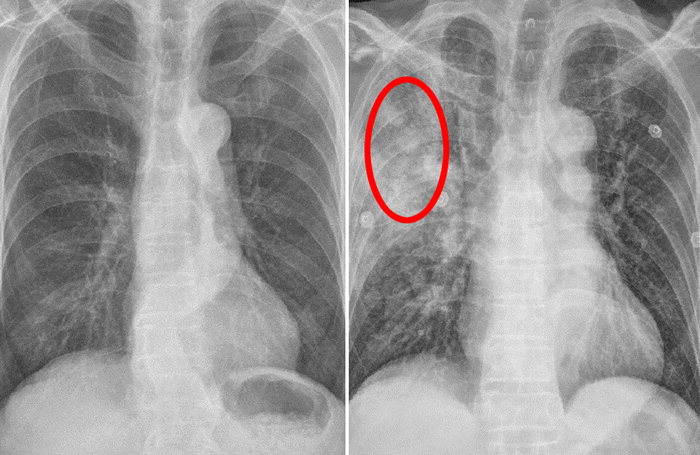

숨가쁨 폐 건강이 좋지 않은데도 숨가쁨 증상이 지속되면 폐암을 의심할 수 있습니다. 폐암 환자의 약 절반이 숨이 가쁘다고 말합니다. 폐의 암 덩어리는 숨가쁨을 유발할 수 있지만 폐암은 또한 흉막 삼출, 허탈된 폐, 상부 기도 폐쇄 등을 유발할 수 있습니다. 흉통 폐암은 다양한 성질의 흉통을 유발합니다. 폐암이 직접 흉벽을 침범하지 않더라도 갈비뼈로 전이되어 통증을 유발하거나 흉막으로 전이되어 지속적인 통증을 유발할 수 있습니다.